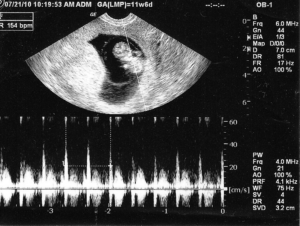

Tim thai bắt đầu hình thành khoảng 20 ngày sau khi thụ thai. Đến tuần thứ 6-7, bác sĩ có thể nghe thấy nhịp tim thai qua siêu âm, đánh dấu thời điểm thai nhi có nhịp tim. Sau tuần thứ 20, nhịp tim trở nên rõ ràng hơn và các bậc phụ huynh có thể cảm nhận được nhịp tim của trẻ mà không cần thiết bị hỗ trợ.

Trong quá trình khám thai, bác sĩ sẽ xác định nhịp tim để đánh giá sức khỏe và sự phát triển của thai nhi, thường sử dụng đầu dò siêu âm chuyên dụng. Từ tuần thứ 11-12, tim thai đã phát triển gần như hoàn chỉnh. Đến tuần thứ 16, tim thai bơm khoảng 24 lít máu mỗi ngày, với nhịp tim dao động từ 120-160 nhịp/phút. Nếu thai nhi hoạt động nhiều, nhịp tim có thể đạt tới 180 nhịp/phút. Sau tuần thứ 20, bác sĩ có thể nghe rõ nhịp tim bằng tai nghe. Nhịp tim mạnh cho thấy thai nhi đang phát triển tốt. Trong giai đoạn chuyển dạ, nhịp tim từ 120-160 nhịp/phút là lý tưởng.